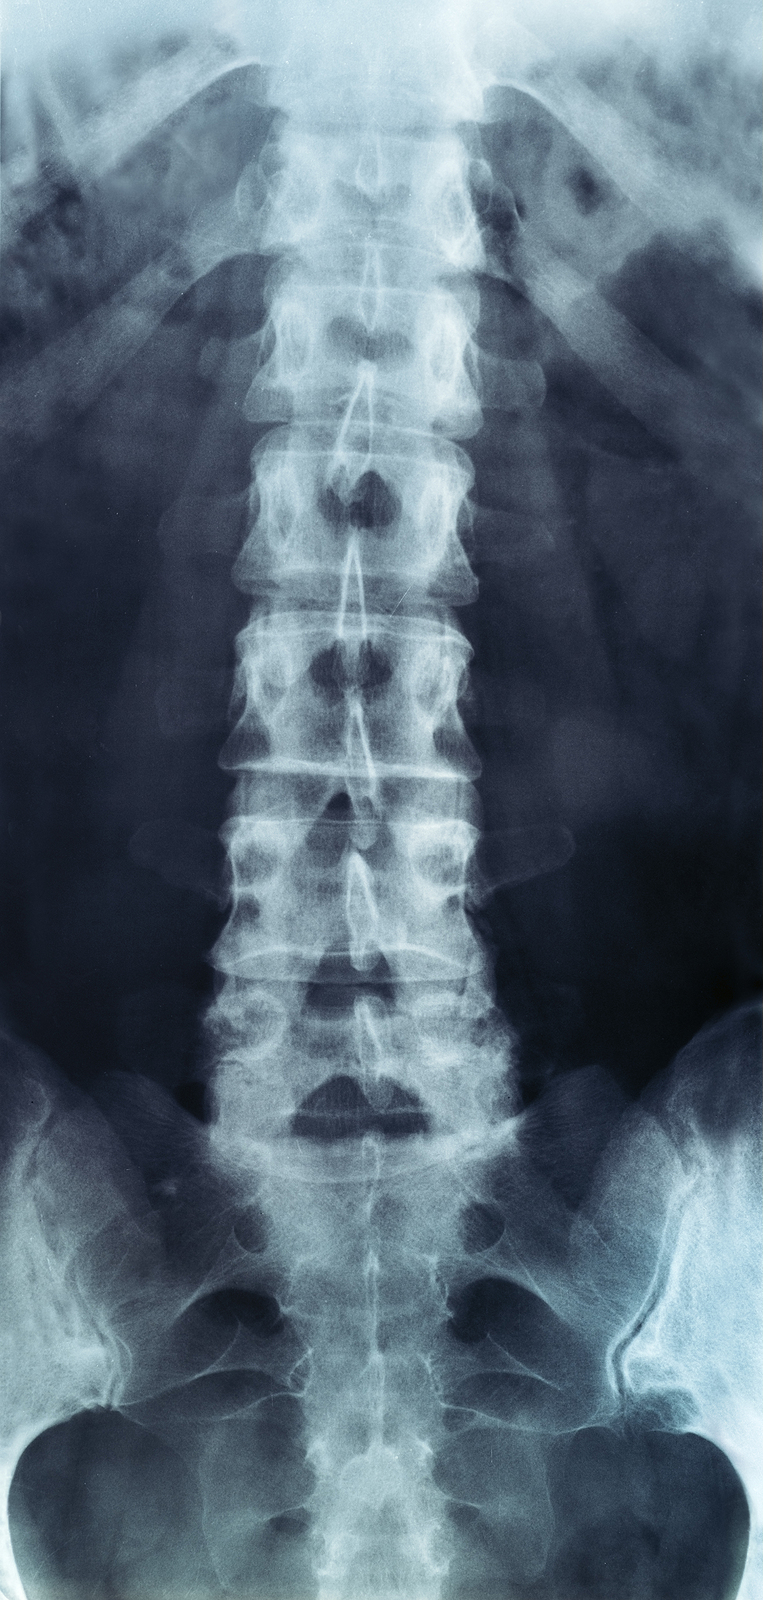

The human spine is made up of 24 spinal bones, called vertebrae, as well as the sacrum and the coccyx. The sacrum is a triangular bone near the bottom of the spine and the coccyx is more commonly known as the tailbone.

Vertebrae are stacked on top of one another to create the spinal column. The spinal column gives the body its form and helps sustain an upright position.

The lumbar spine—where pain is often experienced—is made up of five vertebrae positioned near the bottom of the spinal column. Doctors often refer to these vertebrae as levels L1, L2, L3, L4 and L5. The ‘L’ refers to ‘lumbar’. The lowest vertebra, L5, is connected to the top of the sacrum—a triangular bone at the base of the spine that is located between the two pelvic bones. Some people are born with an extra or sixth lumbar vertebra called L6. Having an extra vertebra doesn't usually cause physical problems.

X-rays are usually the first test ordered before any of the more specialized tests are completed. X-rays use electromagnetic radiation to show problems with bones and can also reveal problems such as fractures, infections, or bone tumors. X-rays of the spine can give your doctor information about bone alignment and can demonstrate how much degeneration has occurred in the spine. Both alignment and degeneration can affect the amount of space in the neural foramina and between the discs, which subsequently impacts the nerves in the area. This is important information your health care professional can use to establish a treatment plan.